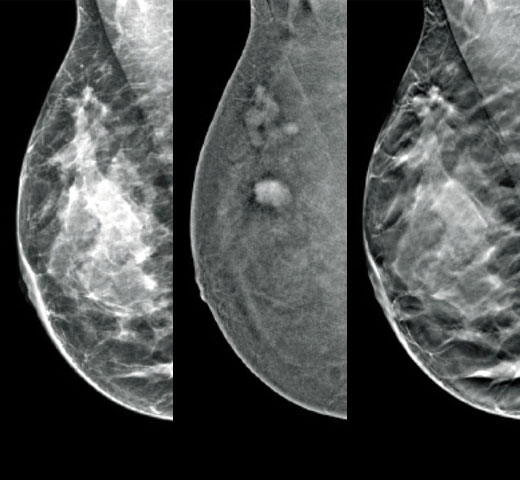

The Selenia Dimensions system delivers proven accuracy of our 3D Mammography exam to detect significantly more invasive breast cancers earlier and reduce call backs vs 2D alone.2-6,*

Diagnose Challenging Patients with Greater Certainty

Clinical Images